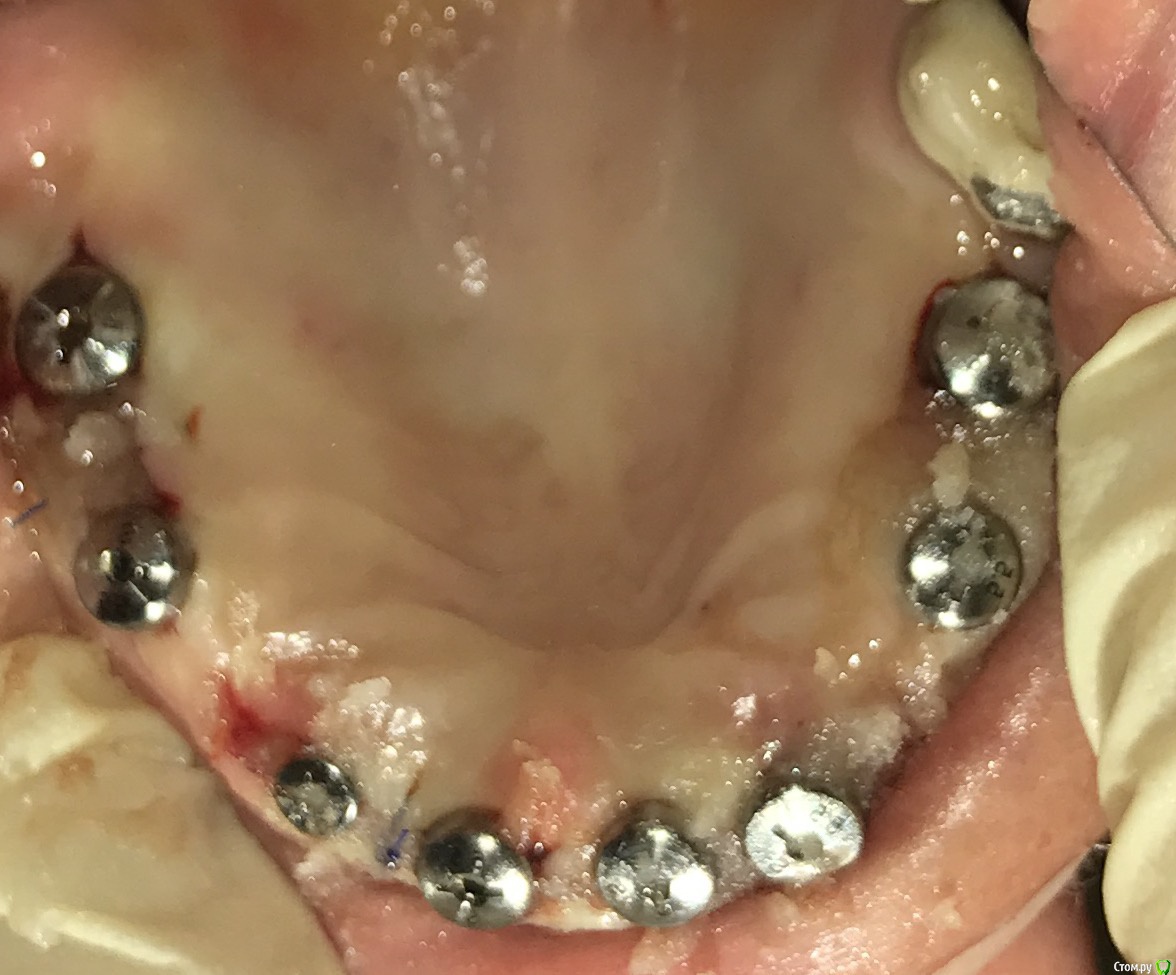

ksenistom Опубликовано 3 февраля, 2017 Поделиться Опубликовано 3 февраля, 2017 Коллеги,подскажите в данном случае есть вариант протезирования без мультиюнитов?Система дентиум.И вообще есть на дентиуме мультиюниты,я с ней недавно начала работать?!Подобная работа на альфе была,там без сомнения мультиюниты выравнивали оси.Снимок сделан сразу после установки формирователей. Ссылка на комментарий

ksenistom Опубликовано 3 февраля, 2017 Автор Поделиться Опубликовано 3 февраля, 2017 С губой все норм,в переднем отделе одномоментная имплантация была,в боковых отделах зубы отсутствовали около 10лет.места достаточно,бананов не должно быть Ссылка на комментарий